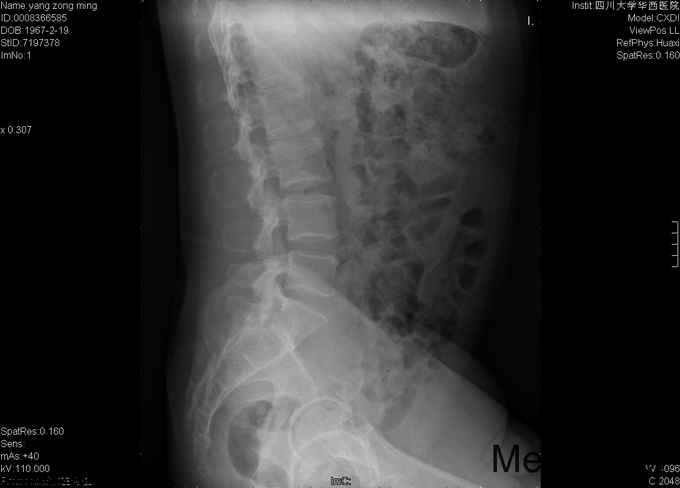

男,48岁8月,因“腰部疼痛伴右腿疼痛1+月”入院。患者1+月前出现腰部疼痛,伴右侧臀部、大腿后部、足背疼痛,大腿后部为主,不影响行走,不伴行走不稳、下肢麻木等,于外院行理疗、针灸等保守治疗,症状未见明显缓解。后症状有所加重,变换体位时疼痛加重,开始出现夜间痛醒,行走困难,遂至当地医院行靶点射频、封闭等治疗(具体不详),效果不佳,于2015-9-28入我院疼痛科,给予对症治疗(具体不详),症状有所缓解,现为进一步治疗入我科。

专科情况:视:双下肢等长,皮肤黏膜完整,无破损,双下肢肌肉无萎缩,脊柱外形正常。触:腰5-骶1棘突间压痛,腰部VAS疼痛评分5分,右下肢VAS疼痛评分6分,右下肢针刺觉减退。动量:四肢肌力、肌张力正常。右侧直腿抬高试验(+),加强实验(+),加强实验(-),双侧髌骨研磨试验(-)。生理反射均正常引出,病理征阴性。辅助检查:2015-9-29数字化X光腰骶椎正侧位摄影示:腰骶退行性病变、骨质疏松。数字化X光胸部正侧位摄影示:心肺未见明显异常。CT椎体一个部位骨三维成像扫描示:1、腰椎退行性病变,L5/S1椎间盘稍向右后突出2、骶管囊肿。MRI腰椎普通扫描示:1、L5/S1椎间盘突出2、腰椎退行性病变。

初步诊断:1、腰5骶1椎间盘突出症;2、骶管囊肿;3、骨质疏松。经皮内镜右侧椎间孔入路腰5骶1椎管减压+椎间盘髓核摘除+射频成形术